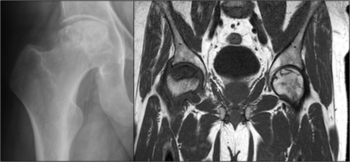

Die Hüftkopfnekrose ist eine Erkrankung zumeist jüngerer Menschen, bei der der Hüftkopf in der Folge einer Durchblutungsstörung (teilweise) abstirbt. Der Auslöser kann ein Schenkelhalsbruch mit Zerreißung der hüftkopfversorgenden Blutgefäße sein. Aber auch ohne einen Bruch können Risikofaktoren wie z.B. hochdosierte Kortisoneinnahme oder Alkoholismus zu einer Hüftkopfnekrose führen. Die Erkrankung verläuft in 4 Stadien, die durch die internationale Gesellschaft für die Knochennekrose (ARCO) beschrieben sind. Das Endstadium ist die Gelenkzerstörung (Arthrose). Häufig tritt die nicht durch einen Bruch verursachte Hüftkopfnekrose beidseitig auf (s. MRT-Bild).

Die Einteilung der Hüftkopfnekrose-Stadien erfolgt gemäß der ARCO-Klassifizierung der internationalen Gesellschaft für Hüftkopfnekrose (ARCO). Im Stadium 0 kann die Erkrankung anhand eines histologischen Befunds diagnostiziert werden. Zu einem frühen Zeitpunkt des ersten Stadiums sind Veränderungen im Kernspin (MRT) zu erkennen. Stadium 2 kann diagnostisch auch durch eine zusätzliche Röntgenaufnahme gesichert werden. Im Stadium 3 und 4 sind die nekrotisierten Anteile des Hüftkopfes klar im Röntgenbild zu erkennen.